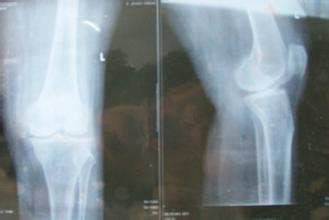

导读: 膝关节骨刺是人体自然老化现象,多由于膝关节在长时间反复使用下导致膝关节磨损、破坏,并促成骨头本身的修补、硬化与增生,多发于中老年人。那么,中老年人膝关节骨刺如何进行保养?下面一起来具体的了解一下。 中

导读: 骨质增生其实是人体骨骼老化的现象,虽然不能避免,但是却可以通过一些方法来延缓衰老,比如多加强锻炼、调节饮食等等,这样可以增强骨质代谢,延缓衰老,推迟骨质增生的到来。